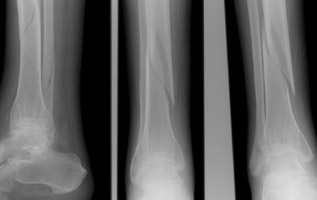

- Click on the image for a larger versionBAP radiograph of the tibia and fibula in a different patient. This demonstrates comminuted and mildly displaced fractures of the distal fibula and tibia.